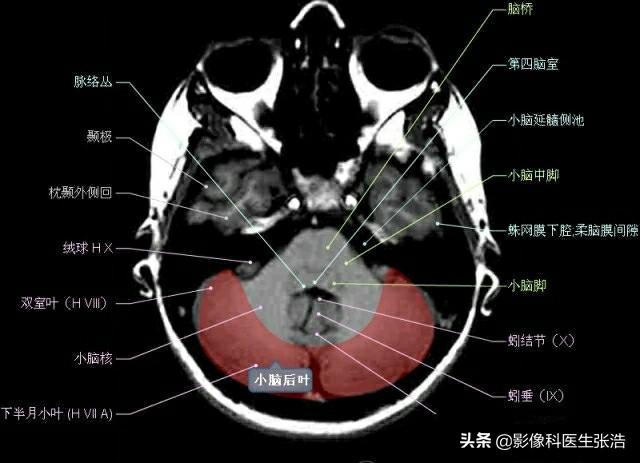

核磁共振(MRI)是一種利用磁場(chǎng)和射頻脈沖來(lái)生成身體內(nèi)部結(jié)構(gòu)的詳細(xì)圖像的非侵入性檢查技術(shù),頭部核磁共振主要用于檢查腦部疾病、神經(jīng)系統(tǒng)問題以及血管狀況等,這項(xiàng)檢查對(duì)于疾病的早期發(fā)現(xiàn)和治療具有非常重要的意義。